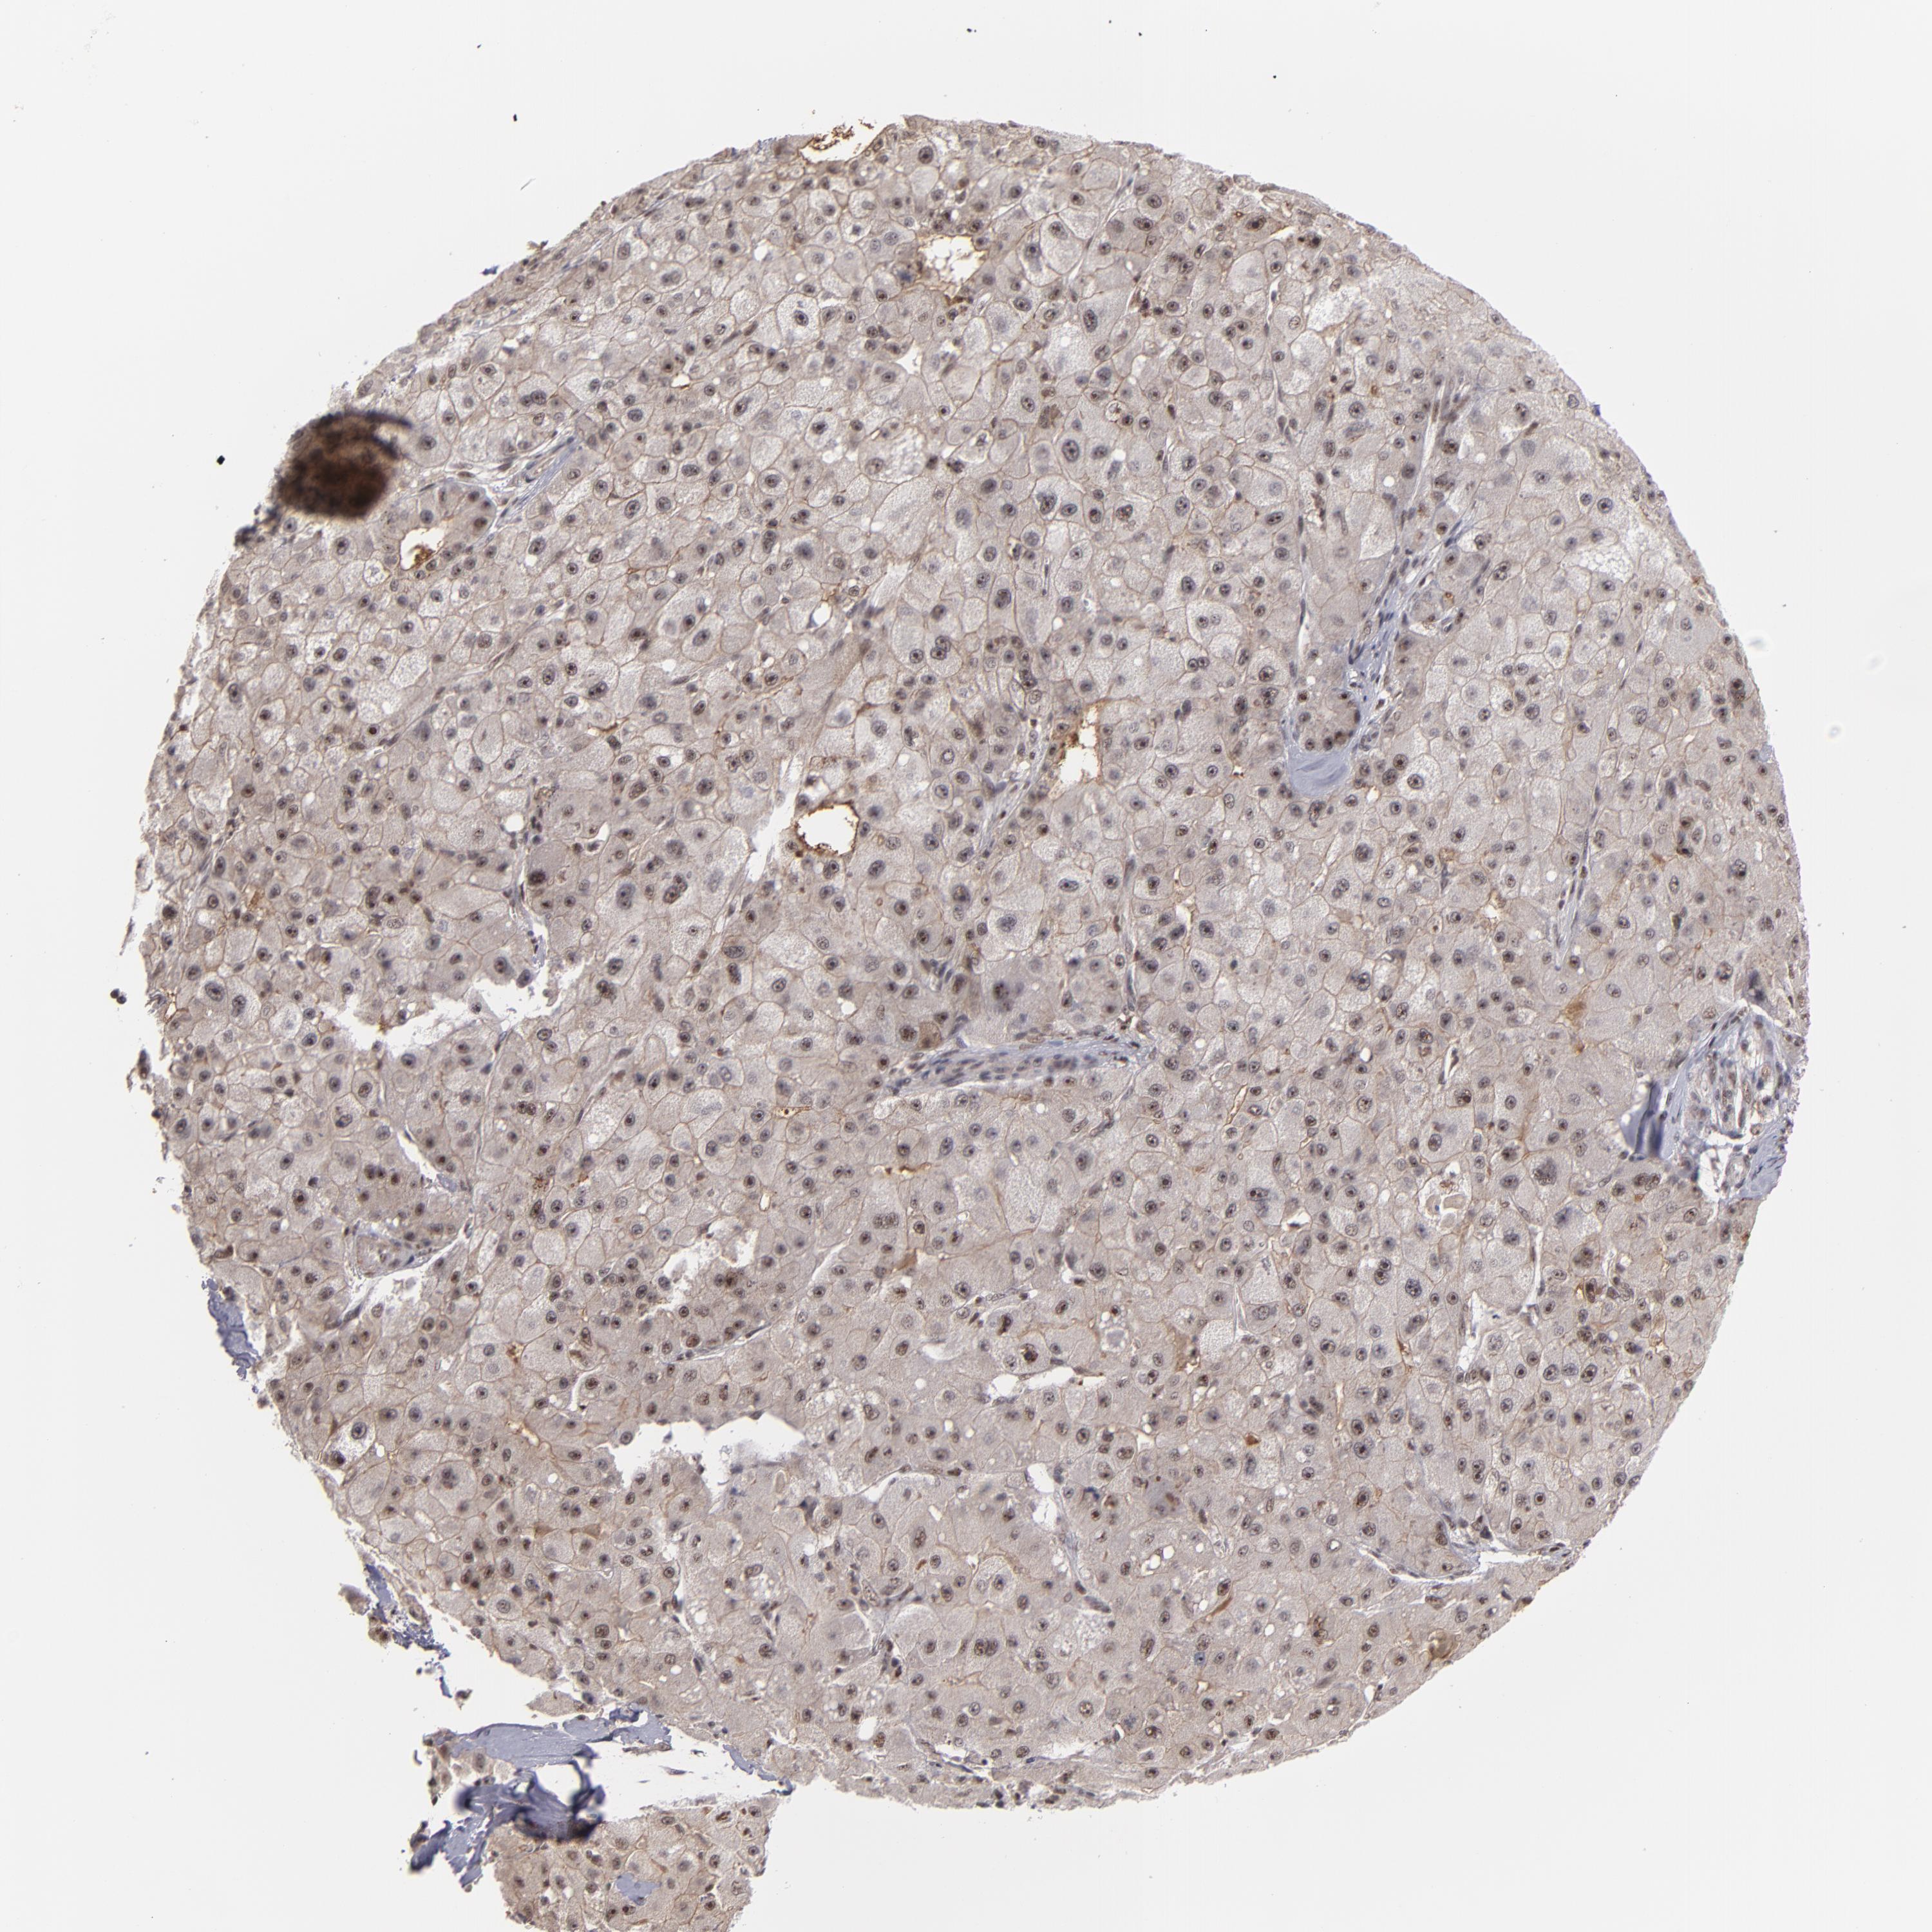

LIVER CANCER - Protein expressioni

A mouse-over function shows sample information and annotation data. Click on an image to view it in a full screen mode. Samples can be filtered based on level of antibody staining by selecting one or several of the following categories: high, medium, low and not detected. The assay and annotation is described here.

Note that samples used for immunohistochemistry by the Human Protein Atlas do not correspond to samples in the TCGA dataset.

Antibody stainingi

Antibody staining in the annotated cell types in the current human tissue is reported as not detected, low, medium, or high, based on conventional immunohistochemistry profiling in selected tissues. This score is based on the combination of the staining intensity and fraction of stained cells.

Each image is clickable and will lead to virtual microscopy that enables deeper exploration of all samples and also displays staining intensity scores, fraction scores and subcellular localization as well as patient and tissue information for each sample.

Antibody HPA001664

Staining

High

Medium

Low

Not detected

Intensity

Strong

Moderate

Weak

Negative

Quantity

>75%

75%-25%

<25%

None

Location

Nuclear

Cytoplasmic/membranous

Cytoplasmic/membranous,nuclear

Cholangiocarcinoma

Carcinoma, Hepatocellular, NOS